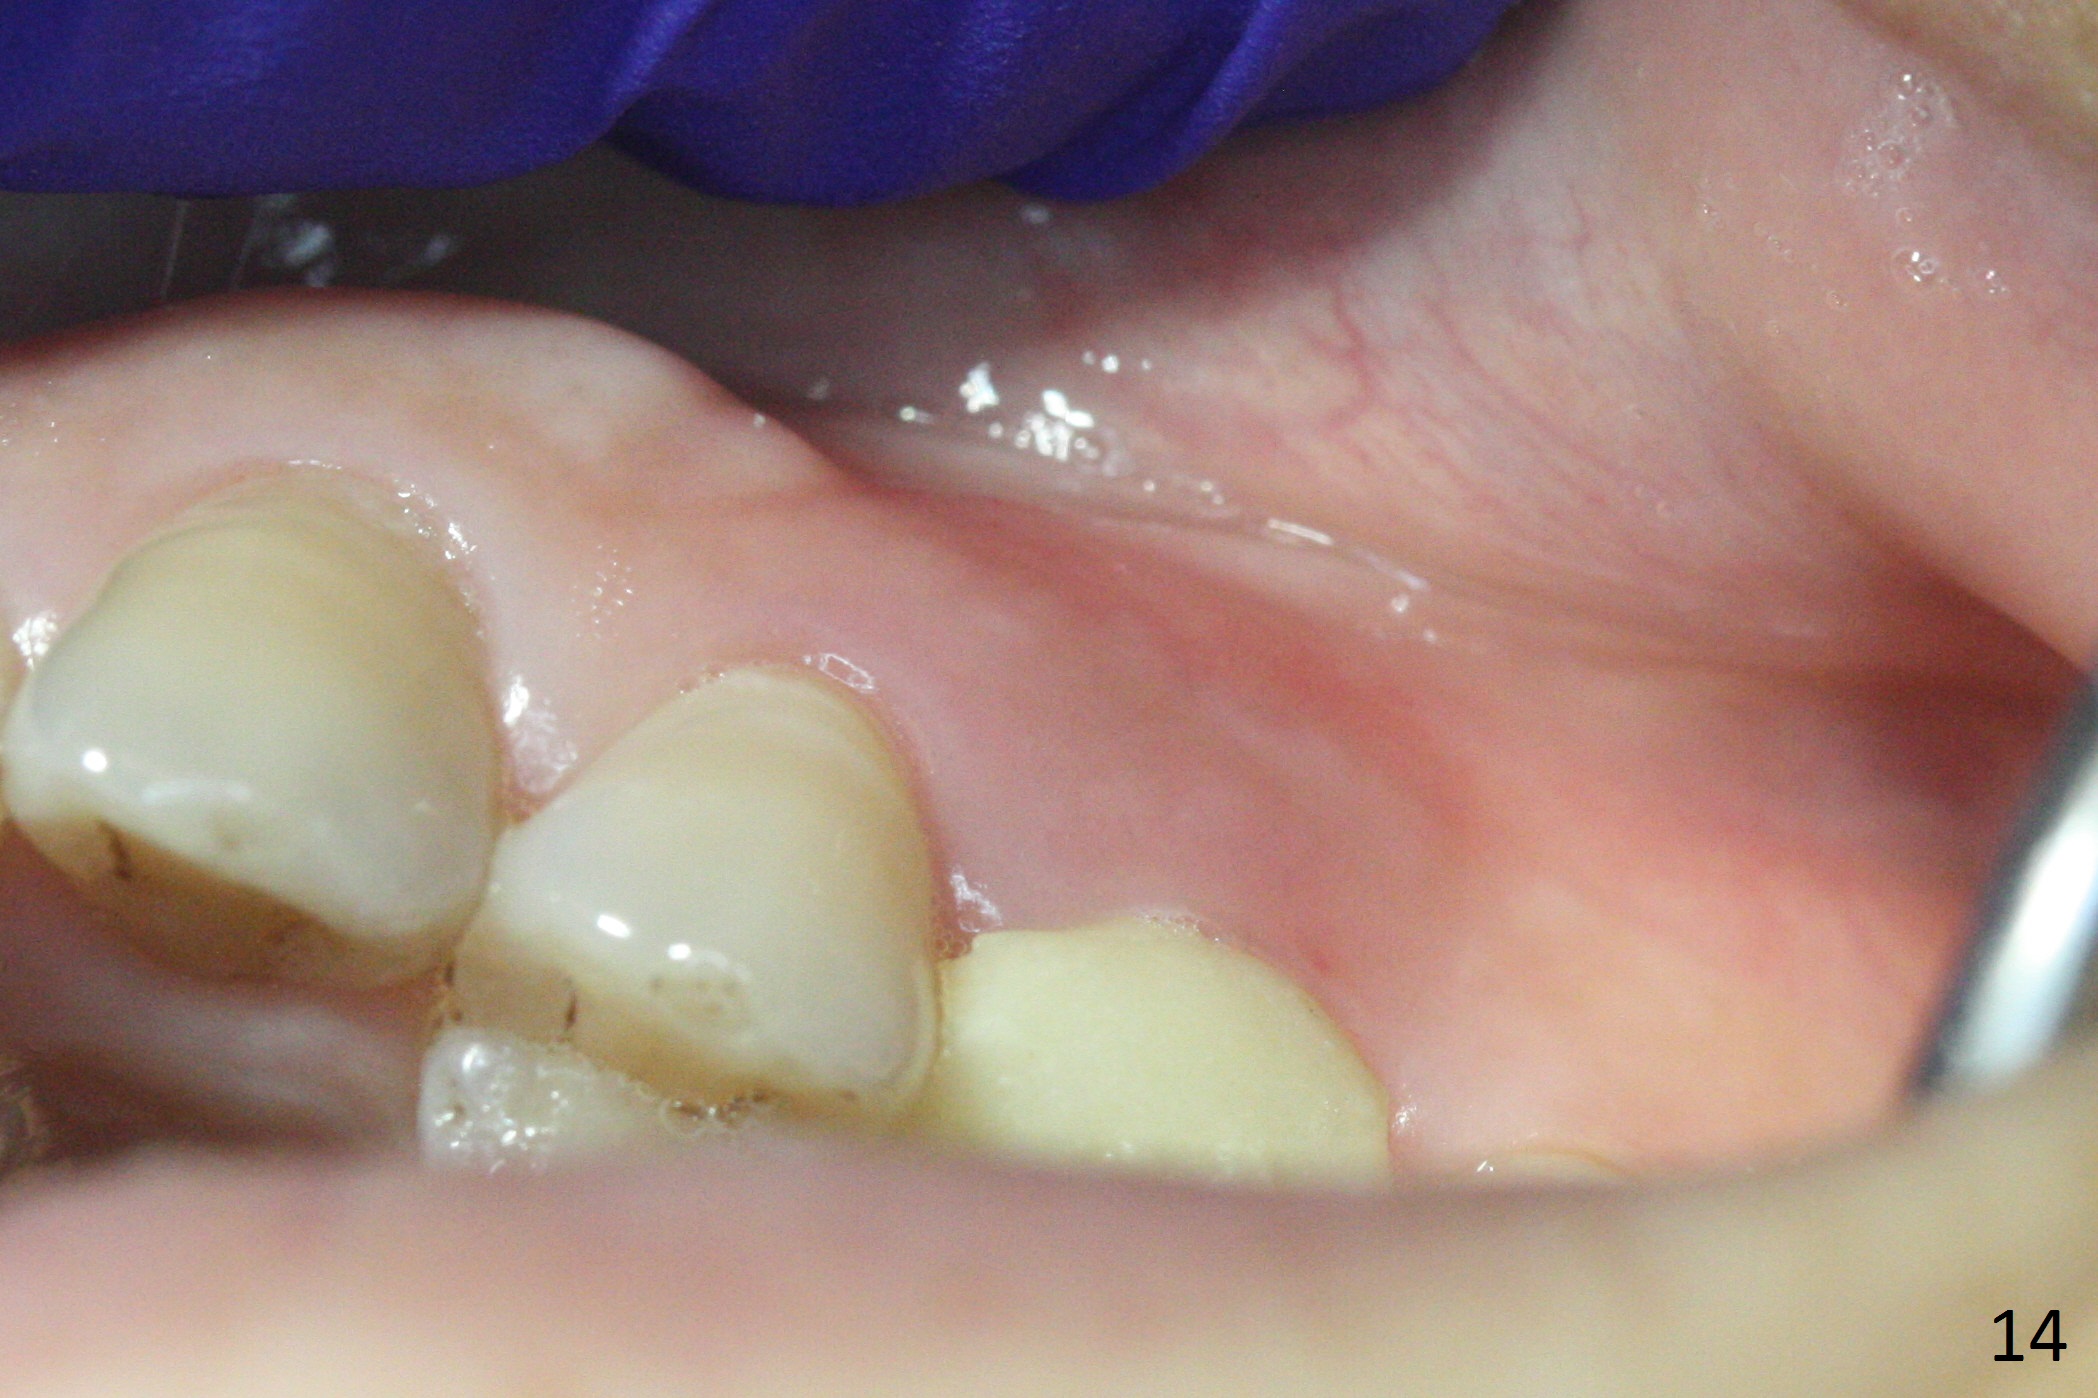

The buccal gingiva over the tooth #13 (Fig.1 white *) with crack (Fig.2 (mesial view of the extracted tooth)) is erythematous with deep buccal (B) pockets, which do not appear to extend the level of exostosis of the neighboring teeth (Fig.1 black *), i.e., coronal to the apical end of the crack with granulation tissue (Fig.2 *). Osteotomy is initiated with a 1.6 mm drill in the palatal aspect of the socket (Fig.3) so that an implant will be placed palatal (Fig.8,11) and there is enough buccal gap for bone graft (Fig.8 *). After withdrawal of 3.3 mm Magic Drill (trephine bur), the osteotomy (Fig.4 O) plug (red outline) is intentionally left in situ. When a 4x11 mm dummy implant is placed (Fig.5 (green outline), 6), the plug is compressed (Fig.5). With placement of a definitive implant (4.5x13 mm, Fig.7 (green), 9), the plug as well as the sinus floor (Fig.4 SF) is lifted (Fig.7 red curved line), 9 (arrowheads)). In brief the autogenous bone is used for sinus lift. There is no intra- or post-op nasal hemorrhage. With a small piece of gauze (Fig.8 G) in the implant well, allograft is placed in the buccal (mainly) and palatal gaps until the level of the implant plateau. Then a 4.5x4(3) mm abutment is placed (Fig.9-10 A). Next another piece of gauze is placed in the space corresponding to the abutment cuff (Fig.11 G) for fabrication of an immediate provisional (Fig.12 P). More bone graft is placed in the soft tissue zone (dual zone technique) after gauze removal and before provisional seating. With dual zone bone graft technique and provisional support, the soft tissue atrophy should be expected to be minimal (Fig.12 *). The zone of exostosis (more coronal) should be much less, since the bone density in the zone is high.

The buccal gingival inflammation subsides 1 week postop (Fig.13,14). There is no bone loss 4 months postop (Fig.15,16). The crown is recemented 6 months post cementation (probably due to short abutment); there is a residual cement (Fig.17 <), which is removed (Fig.18).